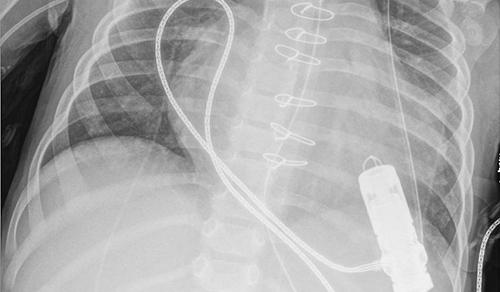

At the Children's Hospital of New York, our pediatric cardiologists, interventional cardiologists, and cardiovascular surgeons from Columbia and Weill Cornell Medicine collaborate seamlessly to manage every form of heart disease in infants and children. Our teams work tirelessly to provide treatments for the most complex heart diseases with the latest imaging technologies, medical therapies, and surgical, transcatheter and hybrid procedures.